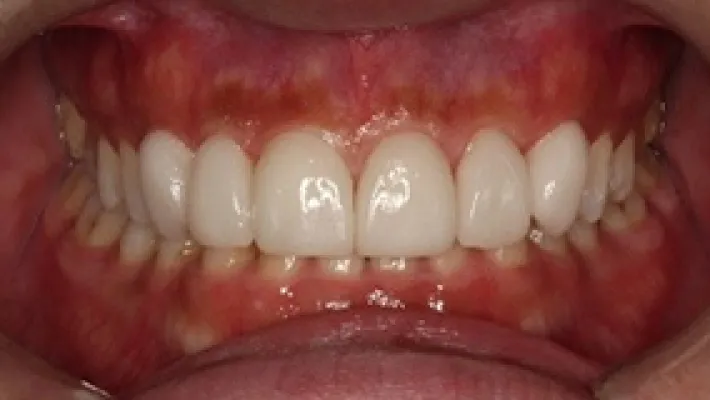

施術後

マウスピース矯正の部分矯正で上下前歯のすきっ歯を改善した症例です。

状態にもよりますが、すきっ歯はマウスピース矯正の得意とするケースの一つです。

効率的な治療計画で最小限の期間と負担で矯正を行いました。

矯正治療の期間・方法

矯正治療の期間や方法は歯並びや顎骨などの状態によって大きく異なります。

矯正治療は歯や歯周組織などに必ずダメージがあります。

矯正治療のダメージを最小限にするために健康的で現実的な治療計画を提案します。

治療費

583,000

治療期間

6.5ヶ月